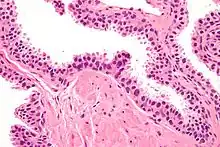

| Micrograph showing high-grade prostatic intraepithelial neoplasia. H&E stain. | |

Histology

Its cytologic features are that of prostatic adenocarcinoma:

- presence of nucleoli,

- increased nuclear-to-cytoplasmic ratio and,

- increased nuclear size.

Microscopically, PIN is a collection of irregular, atypical epithelial cells. The architecture of the glands and ducts remains normal. The epithelial cells proliferate and crowding results in a pseudo-multilayer appearance. They remain fully contained within a prostate acinus (the berry-shaped termination of a gland, where the secretion is produced) or duct. The latter can be demonstrated with special staining techniques (immunohistochemistry for cytokeratins) to identify the basal cells forming the supporting layer of the acinus. In prostate cancer, the abnormal cells spread beyond the boundaries of the acinus and form clusters without basal cells. In HGPIN, the basal cell layer is disrupted but present. PIN is primarily found in the peripheral zone of the prostate (75-80%), rarely in the transition zone (10-15%) and very rarely in the central zone (5%), a distribution that parallels the zonal distribution for prostate carcinoma.[7]

Several architectural variants of PIN have been described, and many cases have multiple patterns. The main ones are tufting, micropapillary, cribriform, and flat. Although these different appearances may cause confusion with other conditions, they have not been found to be of clinical importance. Rarer types are signet-ring-cell, small-cell-neuroendocrine, mucinous, foamy, inverted, and with squamous differentiation.[3]